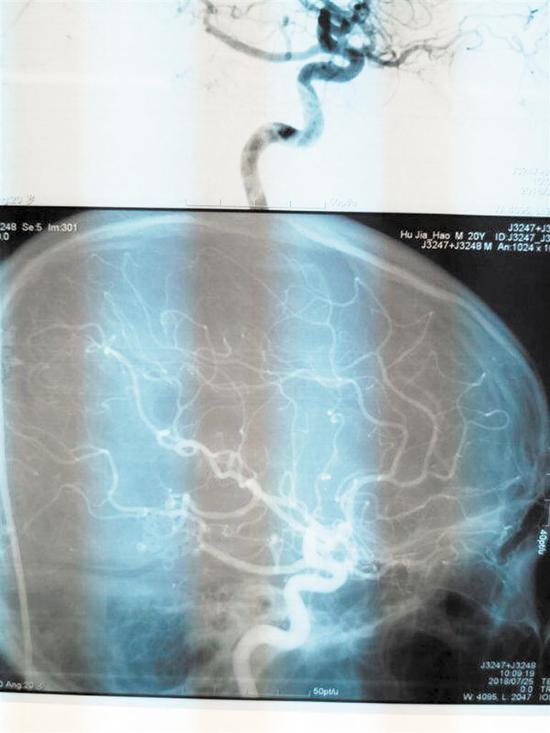

為了隨時觀察小陳的情況,陳淳一直在NICU守護著。“此手術為神經外科4級手術,致殘率、死亡率高。手術后我們一直擔心會有如癱瘓、失明等后遺癥出現,幸運的是,小陳第二天就蘇醒了,神志清醒,無后遺癥出現。復查DSA,他的畸形血管團全切,恢復情況良好。”陳淳說。